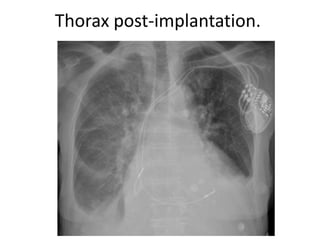

Décision d’up-grading du

PMI-TC en DAI-TC.

Thorax post DAI-TC